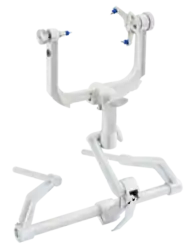

Puma Robotic Arm Aluminum headrest

Aluminum headrest

The main advancements in neurosurgery came about as a result of highly crafted tools. Modern neurosurgical tools, or instruments, include chisels, curettes, dissectors, distractors, elevators, forceps, hooks, impactors, probes, suction tubes, power tools, and robots.[24][25] Most of these modern tools have been in medical practice for a relatively long time. The main difference of these tools in neurosurgery, were the precision in which they were crafted. These tools are crafted with edges that are within a millimeter of desired accuracy.[26] Other tools, such as hand held power saws and robots have only recently been commonly used inside of a neurological operating room. As an example, the University of Utah developed a device for computer-aided design / computer-aided manufacturing (CAD-CAM) which uses an image-guided system to define a cutting tool path for a robotic cranial drill.[27]